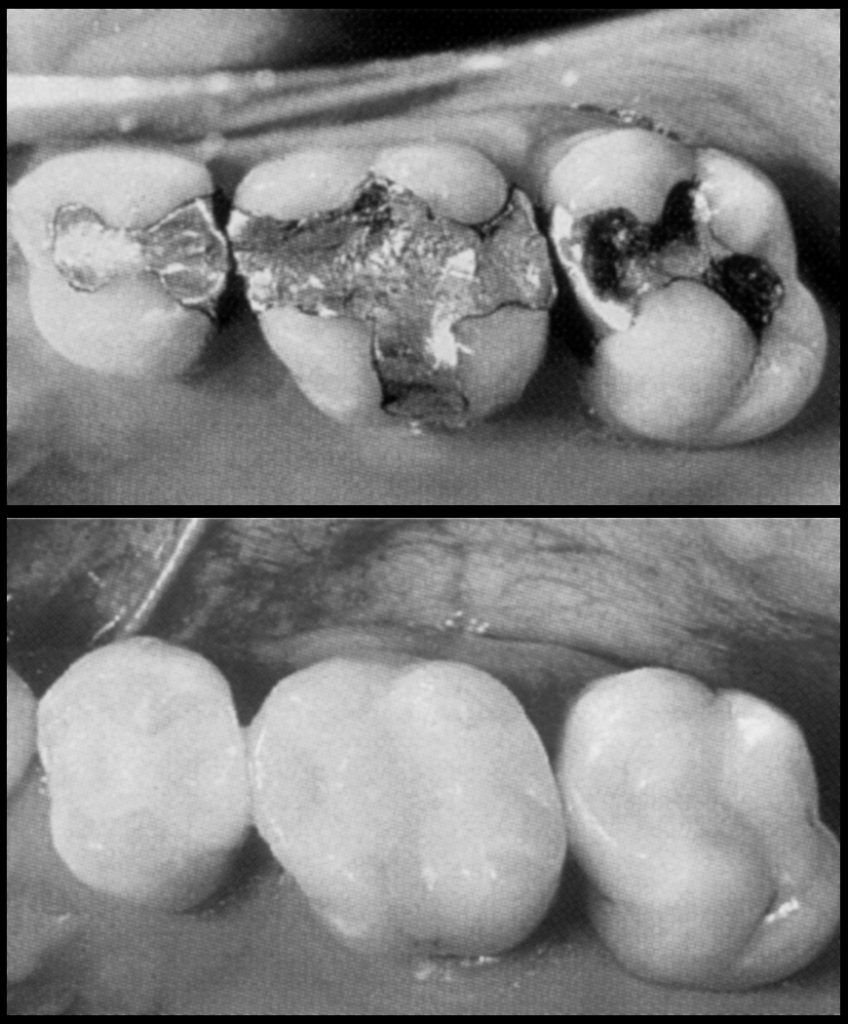

The CEREC system can be used for partial and full crowns, veneers, and in all single-tooth restorations. And yes, in most instances we can replace those unsightly metal fillings with ceramic—with the same characteristics of healthy dental enamel.

Yes, you can have a 100% metal-free restoration that’s as beautiful and natural looking as your original tooth.

There’s never been a better time to replace your old amalgam fillings. We can create a natural and brightened smile your friends, colleagues and family will compliment you on.